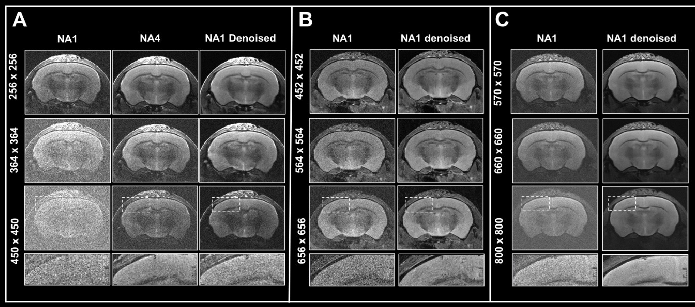

Figure 6. Boosting resolution. Ex vivo T2-weighted TurboRARE data of a fixed mouse head acquired at A) 3 Tesla, B) 7 Tesla, and C) 9.4 Tesla. All images were acquired with 0.8 mm (A) and 0.7 mm (B, C) slice thickness and with a field-of-view of 20 x 20 mm2 and the given matrix size using either no averaging or acquiring 4 averages. Images were reconstructed with no denoising (NA1 and NA4), or after denoising (NA1 Denoised) using a network Large, applying a pre-denoising level of 50% and denoising level of 70%. Image Credit: Bruker BioSpin Group

In Fig. 6, axial T2-weighted TurboRARE images of a fixed mouse head obtained at various field strengths are contrasted. Images were obtained via a fixed field-of-view of 20 x 20 mm2, with 0.8 mm (3 Tesla) and 0.7 mm (7 and 9.4 Tesla) thick slices and with diverse matrix sizes to generate images with various spatial resolutions.

Of particular note, the matrix sizes were made larger by up to a factor of 1.8, 2.6, and 3.1 (vs a matrix size of 256 of the reference protocols) for images obtained at 3, 7, and 9.4 Tesla, respectively. These resolution increases lead to a concomitant loss in SNR for each image. Loss in SNR can be made up for by utilizing averaging and thus additional data was obtained with four averages.

Comparing non-denoised averaged images with single averaged images showed that denoising reduces increased image noise at elevated resolutions and results in images of similar quality to those obtained through averaging.

Improvements in image quality by denoising are more significant with data obtained at 3 Tesla, where heightening the resolution generates images that are more difficult to understand, compared to data obtained at 7 and 9.4 Tesla, where SNR is innately higher.

In any case, images obtained at 7 and 9.4 Tesla are significantly helped by denoising during reconstruction, as the intrinsically elevated SNR of these images can be used for choosing smaller voxel dimensions. Thus, denoising enables researchers to choose higher resolutions within a given unit of time, stemming from a reduced need for averaging. This can also be practical when averaging might be undesirable or impractical.